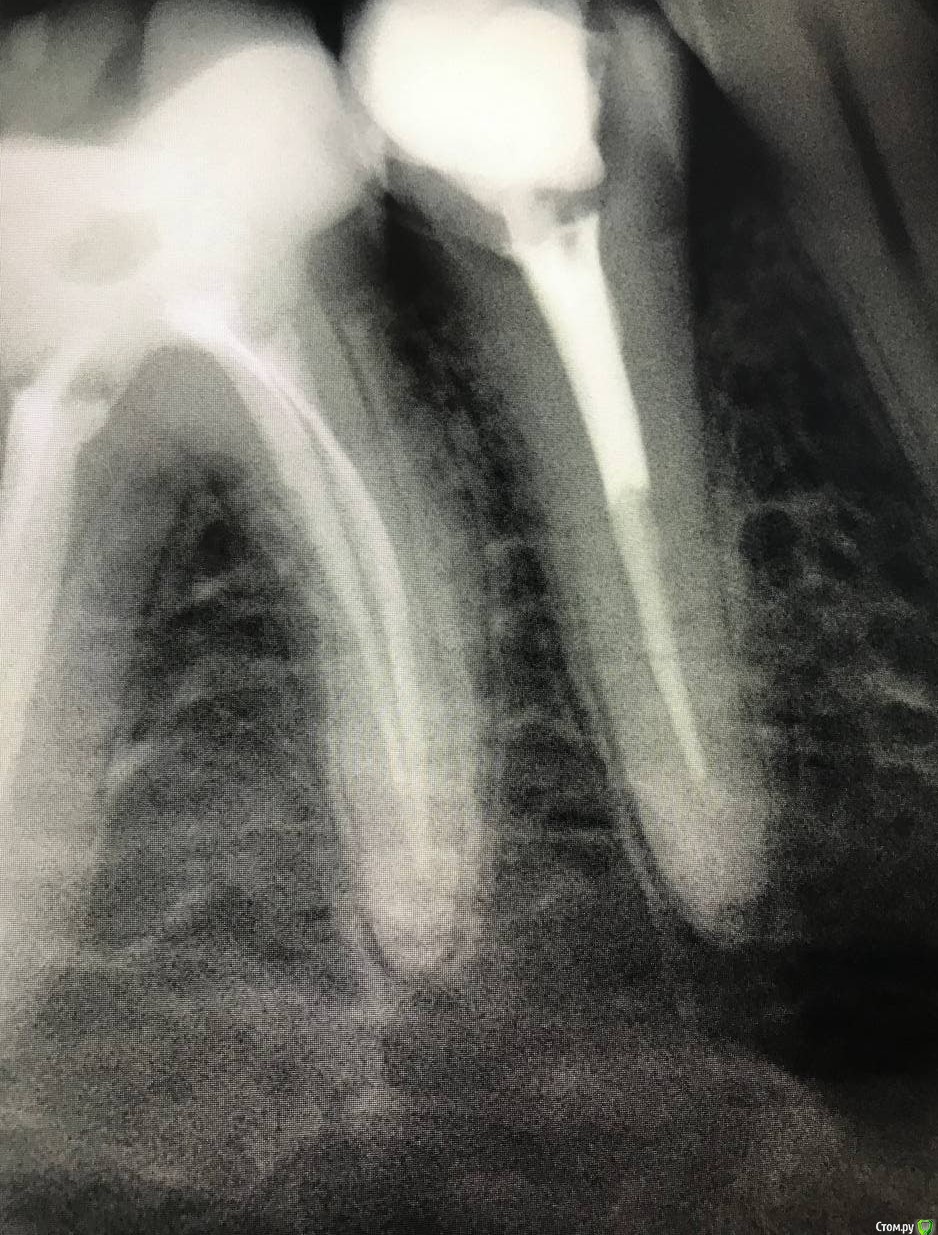

1586Doc Опубликовано 8 февраля, 2020 Поделиться Опубликовано 8 февраля, 2020 5 месяцев назад обратилась пациентка с симптоматикой периодонтита. Оценили, попробовали. Пломбировка вертикалка. 5 месяцев и контроль, боли нет, подвижности тоже. 2 Ссылка на комментарий

1586Doc Опубликовано 10 февраля, 2020 Автор Поделиться Опубликовано 10 февраля, 2020 (изменено) А где контроль на сегодня? При таком качестве снимков оценить будет тяжело.первые 2 фото снимки 9 месяц назад, до ревизии Изменено 10 февраля, 2020 пользователем 1586Doc Ссылка на комментарий